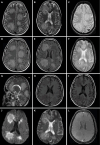

Background: Acute hemorrhagic leukoencephalitis (AHLE), also known as Weston-Hurst syndrome, is a very rare and fulminant form of demyelinating disorder. It is considered a hyperacute and severe variant of acute disseminated encephalomyelitis. Clinically, patients present with fever, headache, seizures, and altered sensorium, which can rapidly progress to coma or death. Magnetic resonance imaging (MRI) is the investigation of choice and plays a pivotal role in diagnosing AHLE. The purpose of this article is to make readers familiar with the typical MRI features of AHLE and to discuss differentials.

Case summary: This case series reports the clinical presentation and typical neuroimaging findings in four patients diagnosed with AHLE. All patients presented with acute neurological symptoms, such as severe headaches, seizures, and altered consciousness, often following a history of fever suggesting an infectious etiology. Additionally, laboratory investigations demonstrated elevated levels of serum inflammatory markers and neutrophilic pleocytosis on cerebrospinal fluid analysis, supporting a post-infectious etiology. MRI findings consistently revealed characteristic white matter lesions with hemorrhagic foci and vasogenic edema, indicative of widespread demyelination characteristic of AHLE. The outcomes varied, with two patients surviving but experiencing neurological sequelae, while two others unfortunately succumbed to the disease. The clinical data, laboratory results, and imaging findings from this case series were systematically compared with those from previously published studies. The key similarities and differences in clinical presentation, imaging characteristics, and outcomes are presented in a tabulated format.

Conclusion: AHLE is associated with high morbidity and mortality rates, emphasizing the need for early recognition, prompt intervention, and multidisciplinary management. Further research is needed to explain the pathophysiological mechanisms underlying AHLE, identify potential biomarkers for early diagnosis, and develop targeted therapies to improve patient outcomes.